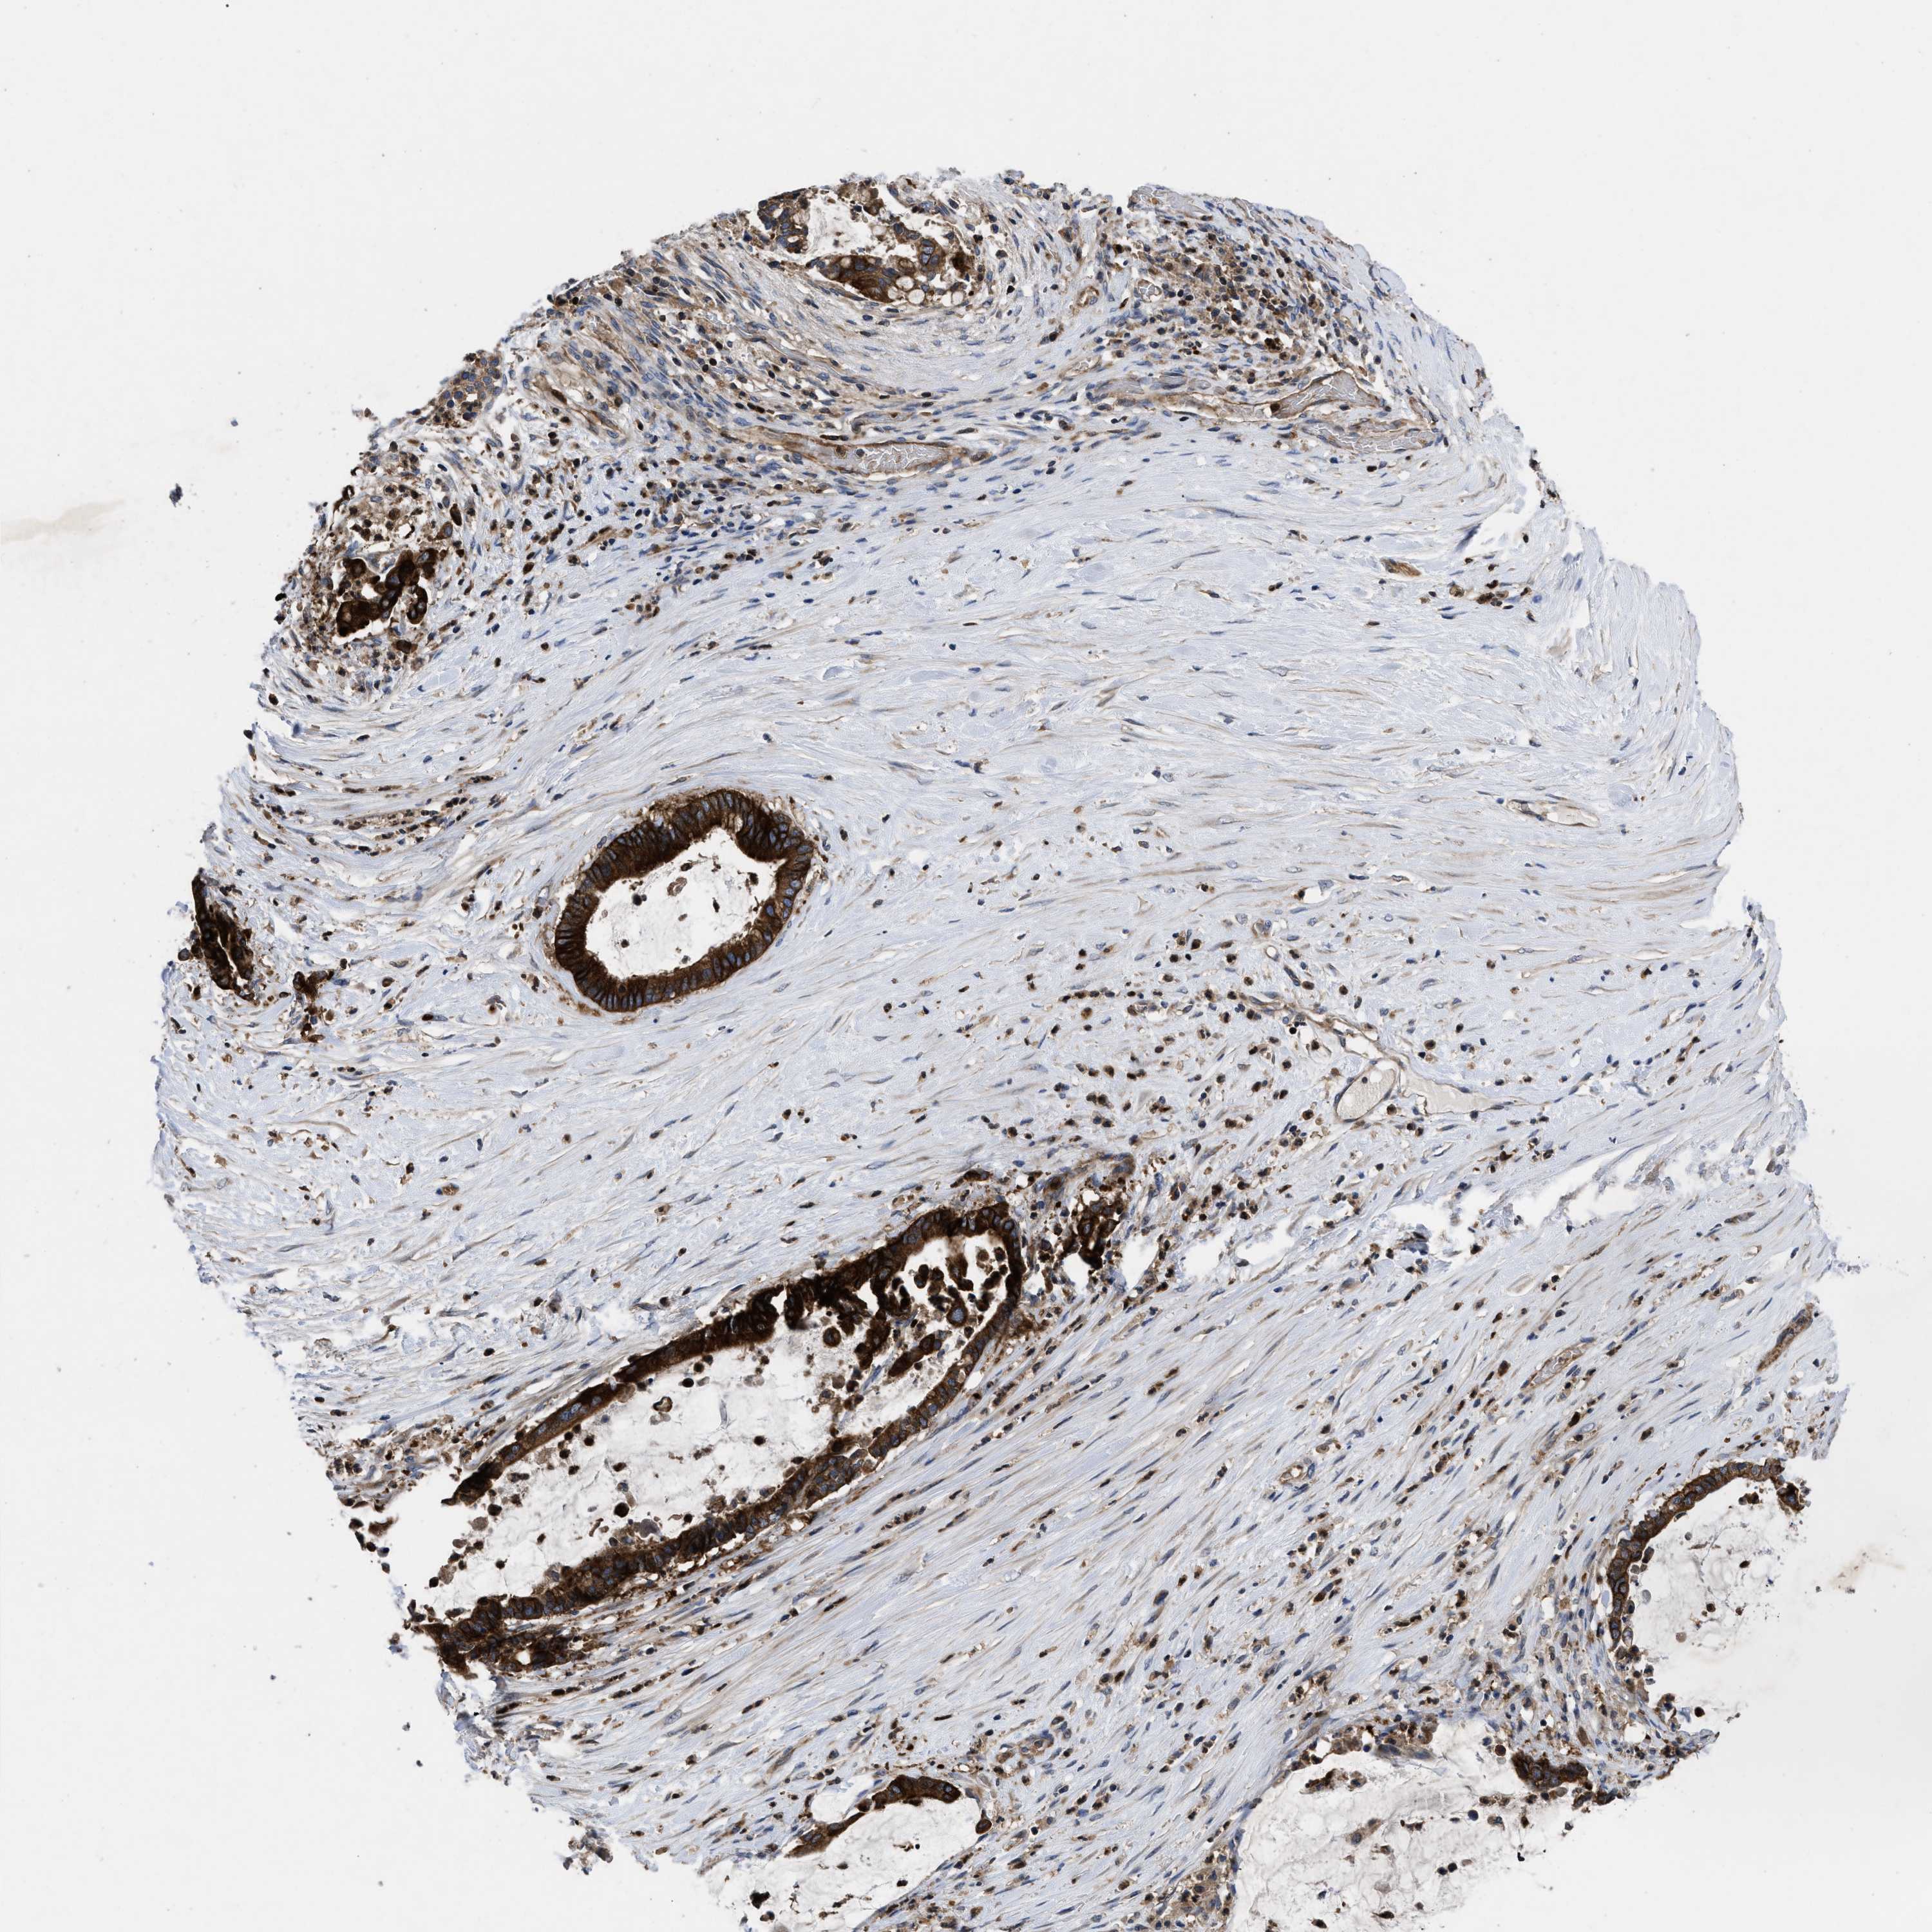

PANCREATIC CANCER - Protein expressioni

A mouse-over function shows sample information and annotation data. Click on an image to view it in a full screen mode. Samples can be filtered based on level of antibody staining by selecting one or several of the following categories: high, medium, low and not detected. The assay and annotation is described here.

Note that samples used for immunohistochemistry by the Human Protein Atlas do not correspond to samples in the TCGA dataset.

Antibody stainingi

Antibody staining in the annotated cell types in the current human tissue is reported as not detected, low, medium, or high, based on conventional immunohistochemistry profiling in selected tissues. This score is based on the combination of the staining intensity and fraction of stained cells.

Each image is clickable and will lead to virtual microscopy that enables deeper exploration of all samples and also displays staining intensity scores, fraction scores and subcellular localization as well as patient and tissue information for each sample.

Antibody HPA018162

Staining

High

Medium

Low

Not detected

Intensity

Strong

Moderate

Weak

Negative

Quantity

>75%

75%-25%

<25%

None

Location

Nuclear

Cytoplasmic/membranous

Cytoplasmic/membranous,nuclear

Adenocarcinoma, NOS